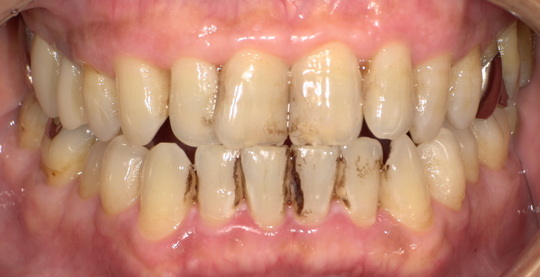

ステイン除去

BEFORE

AFTER

年齢:40代女性

治療内容:エアーフローによる歯の着色汚れ、ステイン除去

治療期間/通院回数:1回

費用: ステインコース 8,800円